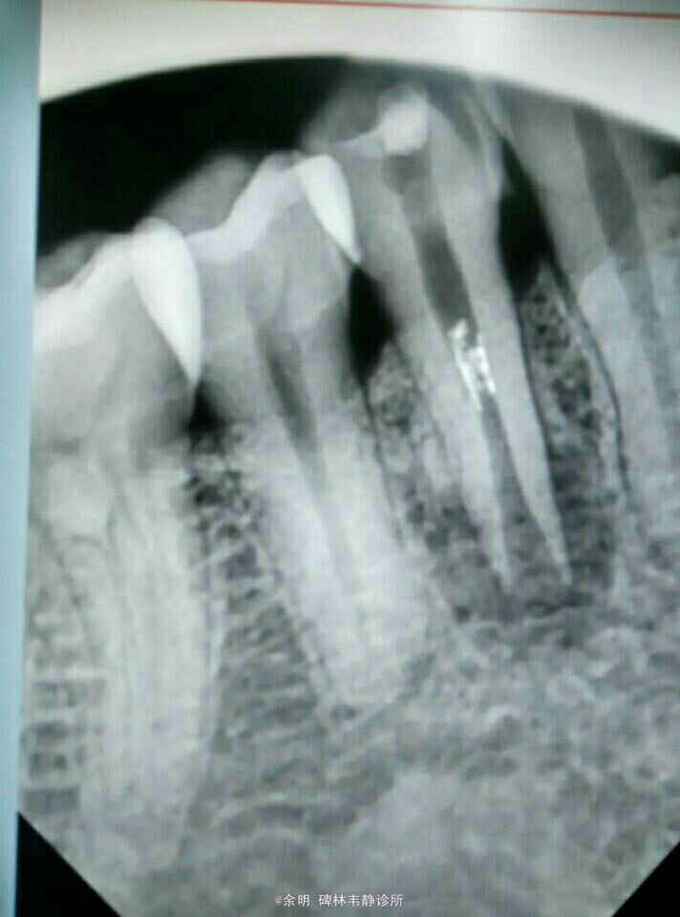

44白色暂封物(去除后可见棉捻),颊侧牙龈可探及瘘管及白色脓性分泌物,叩(+);X线片示:根管口成“喇叭状”,根管中段内可见白色物,根尖阴影。

根尖周炎?根裂?牙内吸收? 处理:44去除暂封料及棉捻,清理髓腔,H2O2.NC冲洗,取出根中白色充填物,隔湿消毒干燥后,手调氢氧化钙暂封 第二次 复诊:44颊侧瘘管未消失,白色脓性分泌物消失,叩(_)。 处理:44去除暂封料,H2O2.NC冲洗,隔湿消毒干燥后,手调碘仿及氢氧化钙暂封。 医嘱:根充后常规医嘱,不适随访。

这个病例还未处理完成,拿出来与大家讨论讨论。 1畸形中央尖一般大都有对称性,检查拍片未见34有中央尖 2牙根纵折早期有冷热痛,咀嚼痛(病人的未有这些症状)(附根纵折的资料), 3根内吸收可见牙冠成粉红色,此病人牙冠未变色 我发出来这个病例:想和大家交流交流,望大家多给宝贵意见,留下这颗牙。